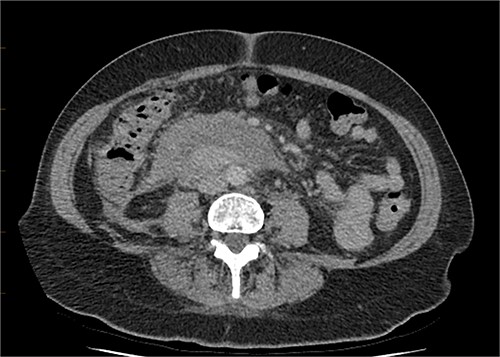

The radiologist suggested a computer tomography (CT) scan to further explore the potential causes for this fluid. The CT abdomen and pelvis revealed extensive oedema and induration surrounding the duodenum with a complex hyperdense fluid, extending from this site to the paracolic gutters and into the pelvis. While these findings are suspicious of a paraduodenal hemorrhage from a ruptured duodenal ulcer and hemoperitoneum, they were not typical for perforated duodenal ulcer or erosion into the blood vessels. Differentials were an infiltrating mass either fibrotic or of a lymphoproliferative origin. However, this could not explain the complex fluid in the abdomen (Figs 1 and 2).

CT abdomen, axial view. Hyperdense fluid centered around the duodenum and tracking into the paracolic gutters. Appearance concerning for paraduodenal hemorrhage, infiltrating mass was considered less likely.